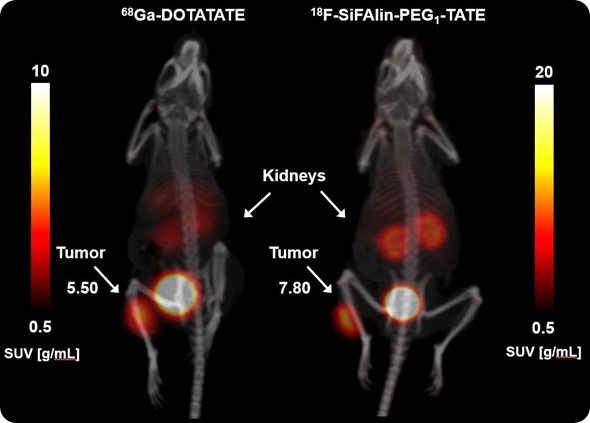

Comparison SUV intensity: 0-90min_1mm Gauss

Image Credit: Bruker BioSpin Group

Another one is the detection of cancer in a gastric cancer model, together with the second medical department here at the University Hospital. Our own research was designing the molecules by multimerization of target structures and then the tests in a mouse tumor model.